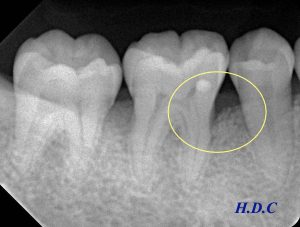

左のレントゲンが初診時、右のレントゲンがエムドゲイン治療後6年経過時です。

初診EMD2EMD6Y

エムドゲインによって、歯の周囲の骨が再生し、長期間安定しているのがわかります(黄色い枠の中)。